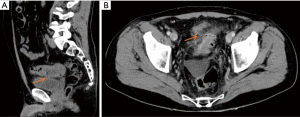

A 55-year-old Caucasian male presented to the emergency room with acute lower abdominal pain and a 1-week history of refractory constipation. He did not report stranguria, pneumaturia, or fecaluria. Past medical history was unremarkable except for multiple recurrent episodes of acute sigmoid diverticulitis. Blood pressure was 130/78 mmHg, heart rate 100 bpm, and oxygen saturation 97% on room air. Body temperature was normal. Physical exam showed mild abdominal distension and tenderness in the lower abdominal quadrants. Abdominal ultrasound showed a small fluid collection in the left lower quadrant. Blood tests showed increased C-reactive protein (13.7 mg/dL) and white blood count (12,500/µL with 86% neutrophils). Plain abdominal X-ray did not reveal free air nor air-fluid images. A CT scan showed a complicated distal left colon diverticulitis with a long segment (7 cm) wall thickening, luminal narrowing (Figure 2A), and multiple perivisceral abscesses (Figure 2B). Moreover, air bubbles inside the bladder were visible (Figure 3), raising the suspicion of a colovesical fistula (Figure 4A,4B). The patient underwent a cystoscopy, which confirmed the presence of a fistula on the posterior-lateral wall of the bladder 2 cm above the vesical trigone (Figure 5). A colonoscopy ruled out the presence of malignancy. The patient was treated with a Foley catheter, clear liquid diet, and broad spectrum antibiotics. Blood tests normalized in a few days, and the patient was discharged home. Readmission for surgical treatment was planned in 3 weeks.